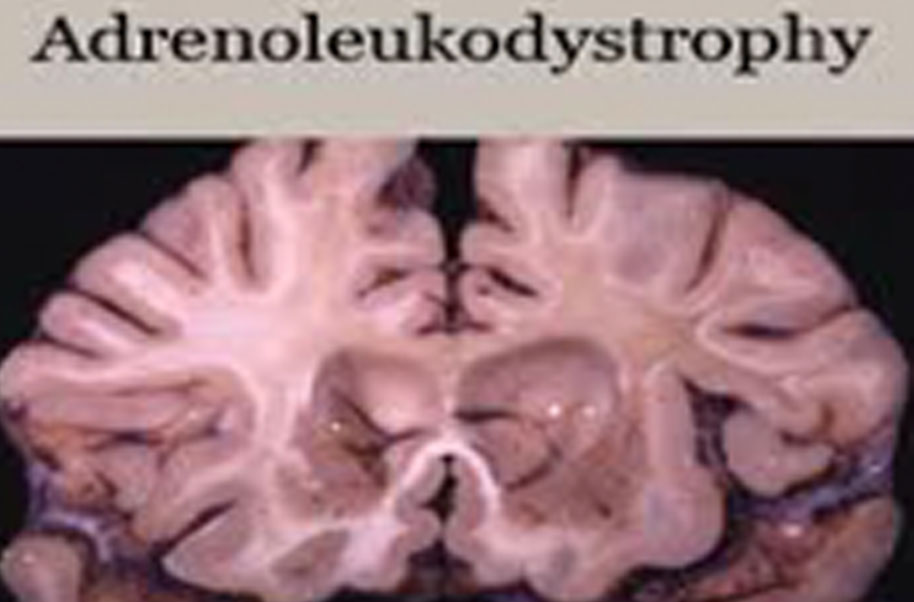

Adrenoleukodystrophy (Ald)

Ald is one of a group of genetic disorders called the leukodystrophies that cause damage to the myelin sheath of the nerve fibers in the brain. The myelin sheath is a fatty covering which acts as an electrical insulator and there are three types of ald.